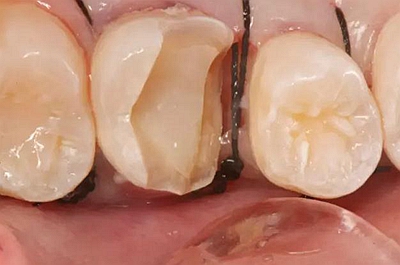

一周后拆除縫線,試戴高嵌體,試戴合適后雙固化粘結。調(diào)合,拋光。

冠延長手術和高嵌體修復,本來需要很多次復診的患者,兩次就診,就把患者難以處理的問題輕松解決了。減少了患者的就診次數(shù)和時間。